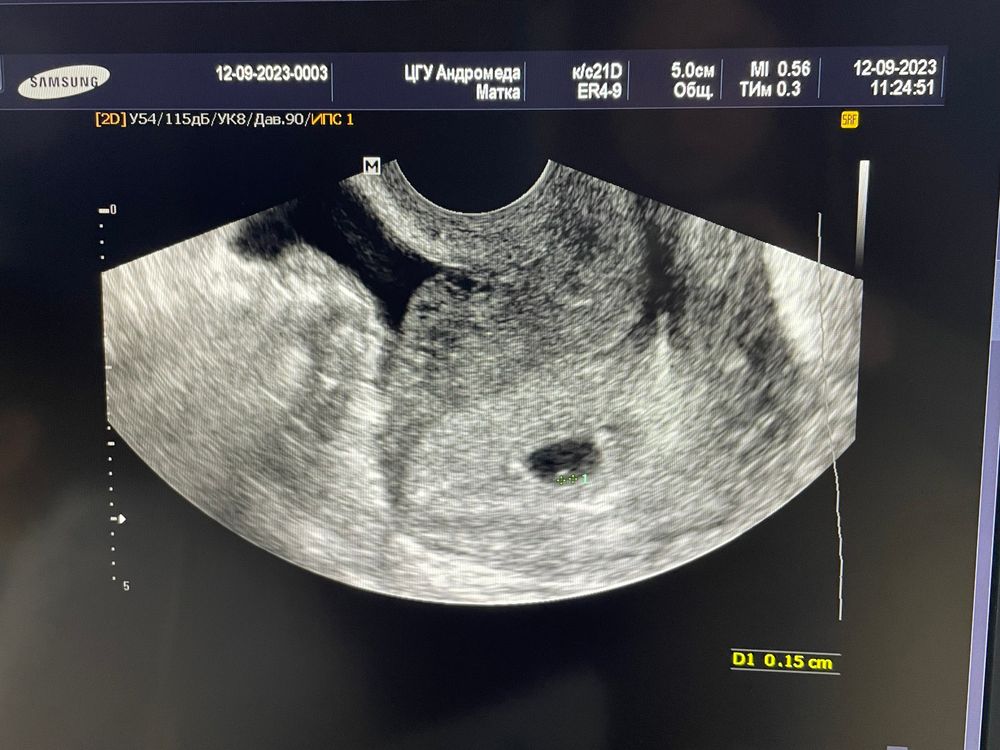

УЗИ. 5 недель.

Малыш прикрепился по задней стенке.

Жт 17мм, жм 1мм, эмбриончик еще не видно. Доктор сказала «очень красивая беременность»☺️ Все в порядке.